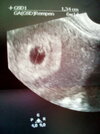

Usg miałam w poniedziałek, widać było pulsujące serduszko :-) jeszcze nie słuchałyśmy, dr powiedziała, że posłuchamy na nast wizycie 31.05.Witaj! Kiedy miałaś usg? Widziałaś serduszko?![]()

Piękna <3 u mnie podobna :-)Termin 04.01

Czekam jak fasoleczka będzie się rozwijać